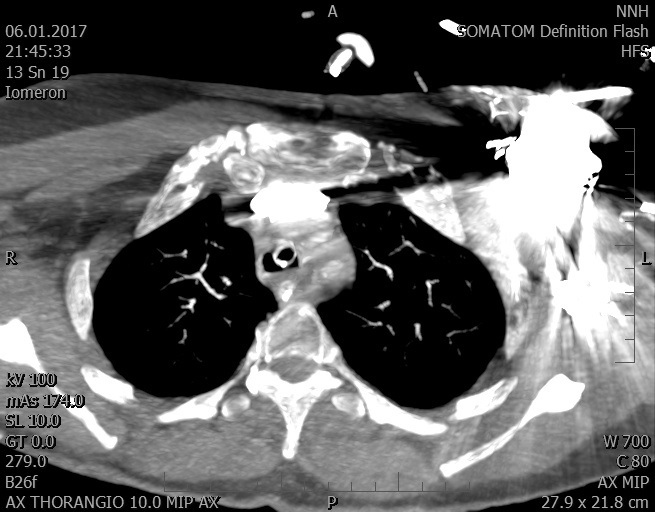

Video 1 - Akutní koronarografie prokázala normální nález na věnčitých tepnách s výjimkou suspekce na lehký spasmus na pravé koronární tepně.Echokardiograficky byla zjištěna těžká dysfunkce dilatované levé komory s nezvětšenou pravou komorou (video 2).

Video 2 - Echokardiograficky byla zjištěna těžká dysfunkce dilatační levé komory s nezvětšenou pravou komorou.Pro nejasnou příčinu zástavy jsme provedli i vyšetření výpočetní tomografií (CT), které vyloučilo plicní embolizaci (série 1 - soubory na konci článku). V den přijetí při přetrvávající oběhové nestabilitě byla nemocná opakovaně defibrilována pro fibrilaci komor se stabilizací rytmu po podání amiodaronu a mesocainu. Dle hemodynamických měření se jednalo o těžký kombinovaný šok. Vstupní laboratorní vyšetření bylo bez větších pozoruhodností. Posléze jsme doplnili anamnézu od příbuzných a zjistili, že pacientka užila do dvou hodin před srdeční zástavou první tabletu amoxicilinu na lehký respirační infekt. Při nevýtěžnosti vstupních vyšetření a nových anamnestických informacích jsme doplnili 14 hodin po kolapsu vyšetření koncentrace tryptázy v séru, která byla extrémně zvýšena (tabulka 2), což nás vedlo k podezření na anafylaxi.